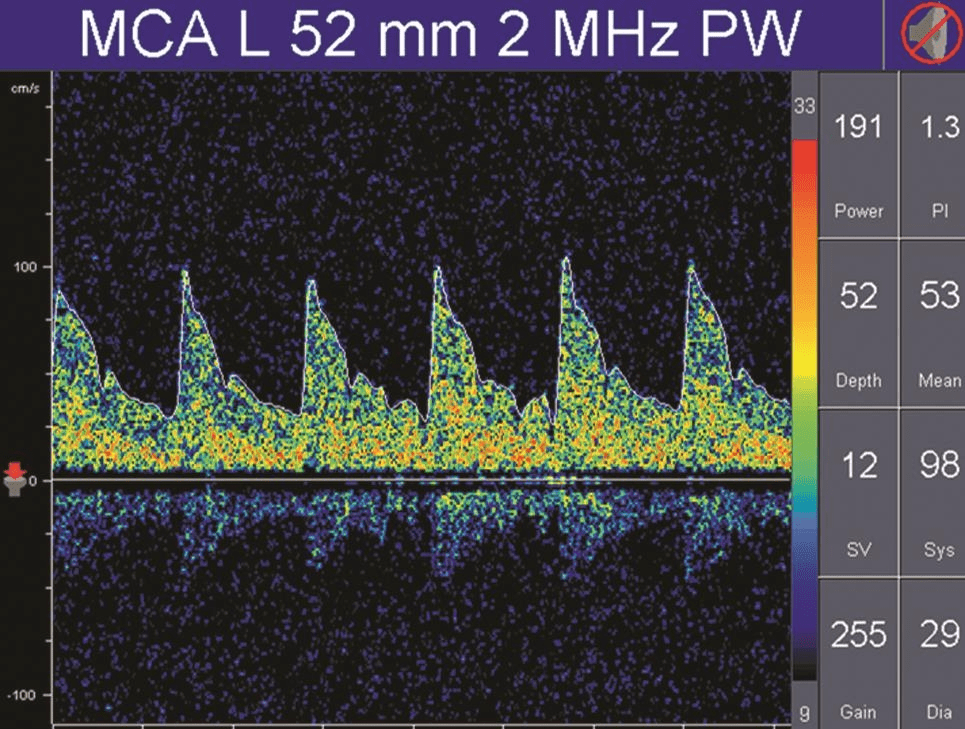

正常情況下顱內(nèi)血管的血流頻譜為相對低搏動性波形(PI值為0.55~1.05),而外周血管(顱外頸動脈或肢體血管)為相對高搏動性或高阻力波形(PI值通常大于1.05),顱內(nèi)正常搏動指數(shù)和阻力指數(shù)的頻譜(詳情見下圖)。

而高阻力頻譜則見于顱內(nèi)壓增高、大動脈嚴(yán)重狹窄或閉塞的近端血管,以及長期高血壓受檢者(詳情見下圖)。

TCD多普勒高阻力血流頻譜